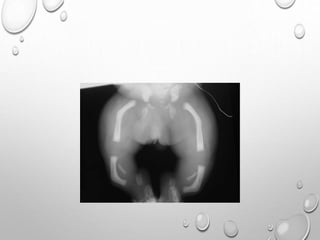

• 1. DYSPLASTIC OR SQUARE

ILIAC BONES

2. NARROW SACRO-SCIATIC

NOTCHES

3. FLAT BILATERAL

ACETABULAR ROOFS

4. SHORT BOTH FEMORAL

NECKS

5. CHAMPAGNE GLASS-

SHAPED PELVIC CAVITY